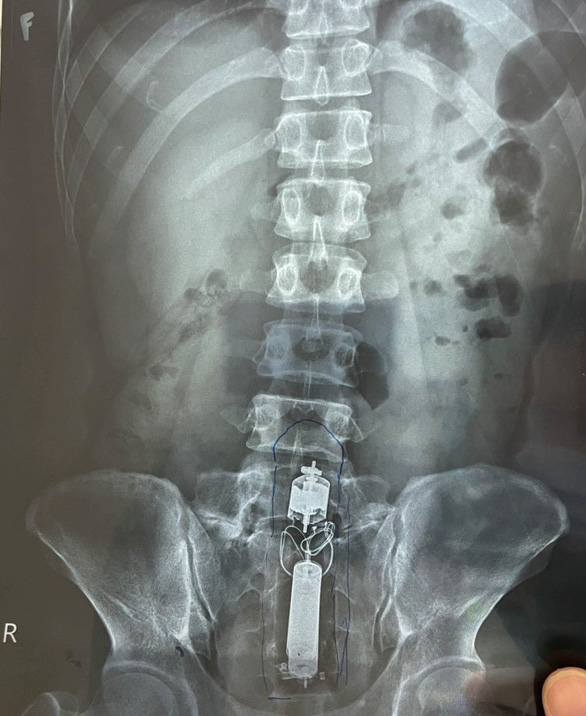

직장에 성인용 장난감이 끼어 응급실 입원한 남성 환자

호치밍 시 175 군의료병원은 방금 내시경 검사에서 나온 이물질은 남자환자가 사용하던 성인용 장난감으로, 사용과정에서 '장난감'이 직장까지 내려왔기 때문이라고 밝혔습니다.

남성 환자 LNHT(31세)는 직장 속 항문의 많은 부위 통증으로 입원했습니다. 엑스레이 검사에서 의사는 직장에서 '희귀한' 모양의 이물질이 있음을 발견했습니다.

*이런 경우 개복 수술이 어려워 개복없이 2-3시간 소요 후 다행히 꺼냈다고 합니다. ㅎㅎㅎ